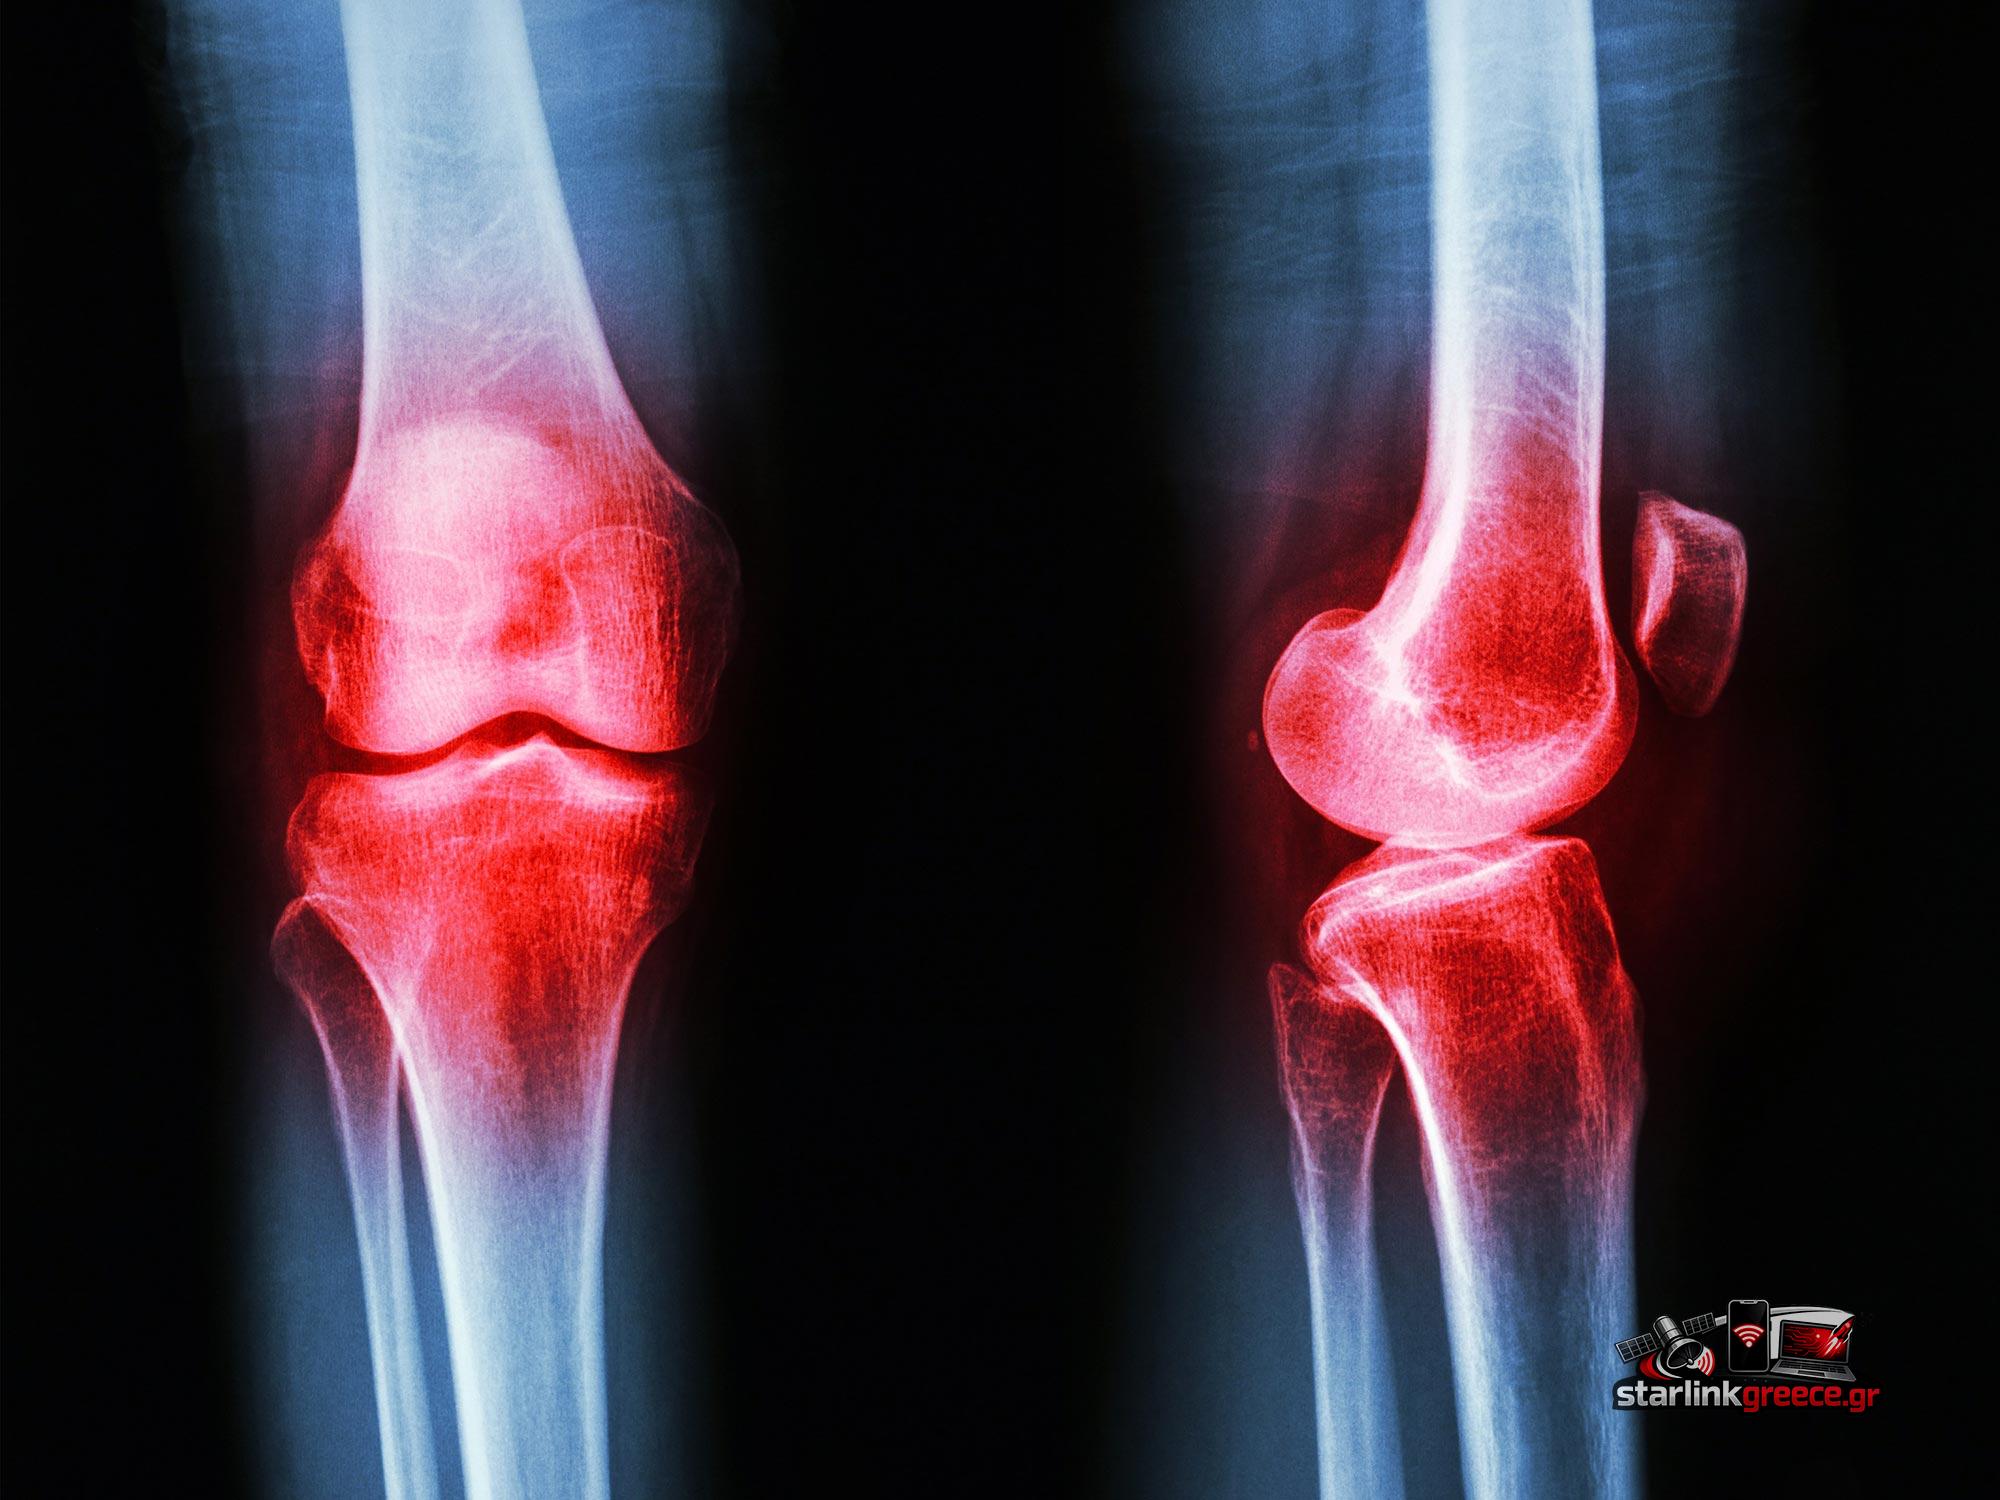

Τι Είναι η Αρθρίτιδα;

Η αρθρίτιδα δεν είναι μια μεμονωμένη ασθένεια, αλλά μια ευρεία κατηγορία διαταραχών που πλήττουν τις αρθρώσεις. Ορισμένες από τις πιο κοινές μορφές περιλαμβάνουν:

- Οστεοαρθρίτιδα: Μια εκφυλιστική πάθηση που προκύπτει από τη φθορά του χόνδρου στις αρθρώσεις.